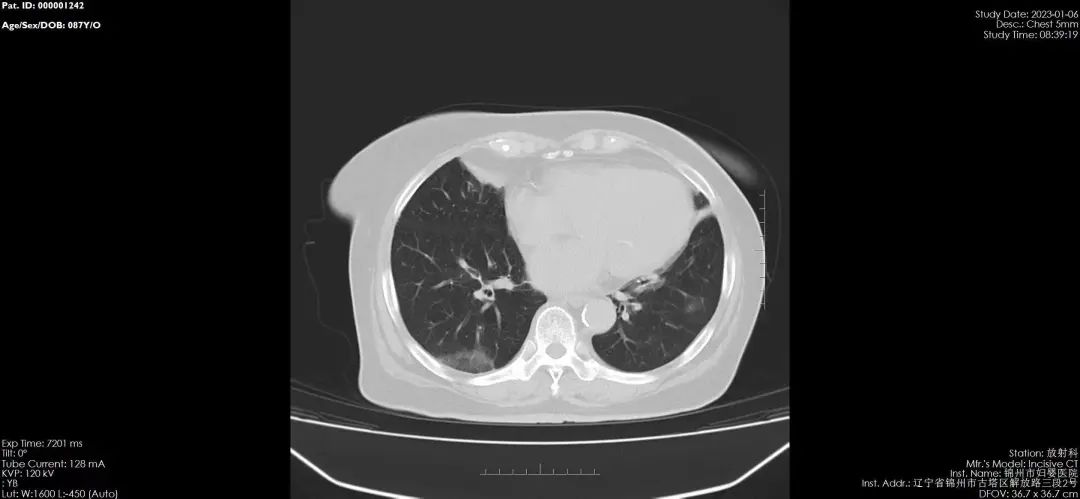

鉴于新冠病毒感染后容易出现肺部感染和肺部炎症等情况,很多感染者有肺CT检查的需求,为了让患者得到及时的检查,锦州市妇婴医院(妇幼保健院)积极开展成人及儿童的肺CT检查诊疗服务,并推出门诊优惠活动,费用降为210元,无需预约,即来即检。

新冠肺炎CT的影像学表现:在疾病的早期,患者可以出现多发的斑片影,为淡片状的渗出影。随着疾病的进展,双肺影像学会出现加重,为双肺、多肺叶、多肺段的渗出影,可以为间质性病变。

在病程7天左右,患者的肺CT可以出现加重,而导致双肺弥漫性的间质纤维性病变。重型和危重型病例可发生肺实变表现为白肺,患者出现呼吸衰竭,因此即便“症状较轻”也千万不能轻视。上呼吸道感染如果不及时治疗会进展肺部也会出现阴影,如咳嗽剧烈、伴有明显气短或者出现咳大量黄痰,甚至出现痰中带血、伴有反复发热、进行性加重的呼吸困难、胸痛等新发症状或原有症状加重时,应及时完善肺CT检查。